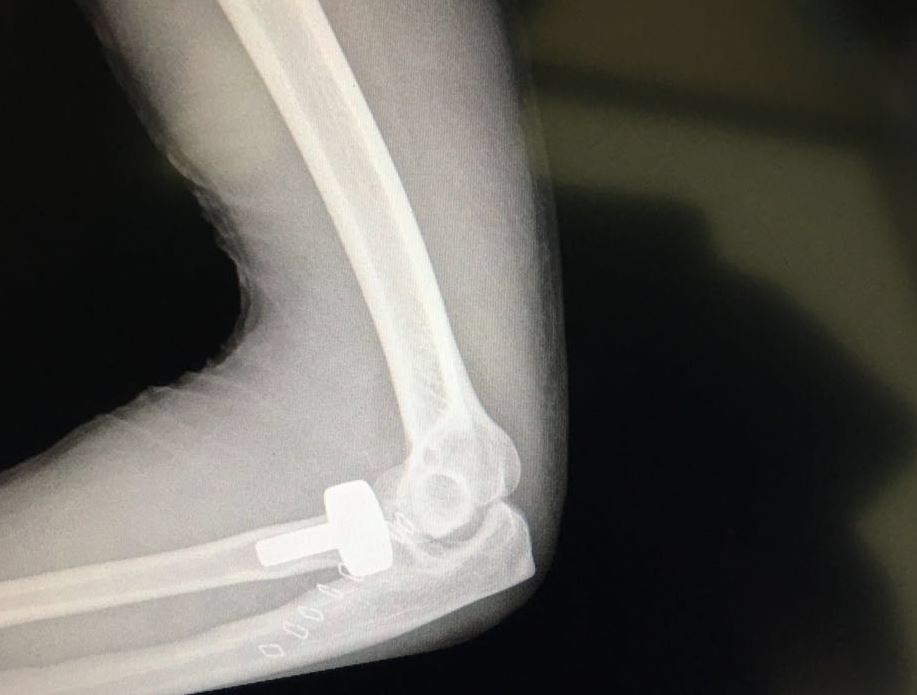

نجح فريق طبي كويتي في الاستعاضة عن عظمة رأس الكعبرة (إحدى عظمتي منطقة الساعد التي توصل المرفق بالرسغ) بمفصل صناعي لوافد آسيوي سقط من علو أثناء عمله.

وأضاف جراغ الذي يشغل أيضا منصب استاذ مساعد في كلية الطب بجامعة الكويت أن العملية التي استغرقت نحو ساعة واحدة كانت معقدة إثر تهشم عظمة (رأس الكعبرة) إلى سبع قطع ما صعب من عملية تثبيت الكسر بـ «البراغي» المعتادة.

وأوضح أن الفريق الطبي تمكن من تبديل العظمة المتهشمة بمفصل حديدي في حين تم الاعتماد على الأشعة المباشرة في غرفة العمليات لتحديد مسار البراغي.

ولفت إلى أن عظمة (رأس الكعبرة) تشكل جزءا كبيرا ومهما من مفصل الكوع، موضحا أنه في حال تهشمها إلى أكثر من ثلاث قطع يكون تبديل المفصل ضروريا.